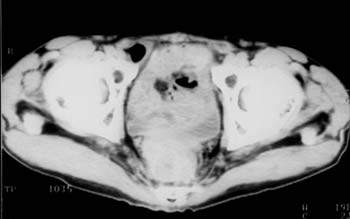

Рис. 3. Рецидив. Через 11 мес после операции между крестцом и мочевым пузырем определяется дополнительное мягкотканное образование. Семенные пузырьки не дифференцируются. Внутри опухоли участок снижения плотности - некроз.